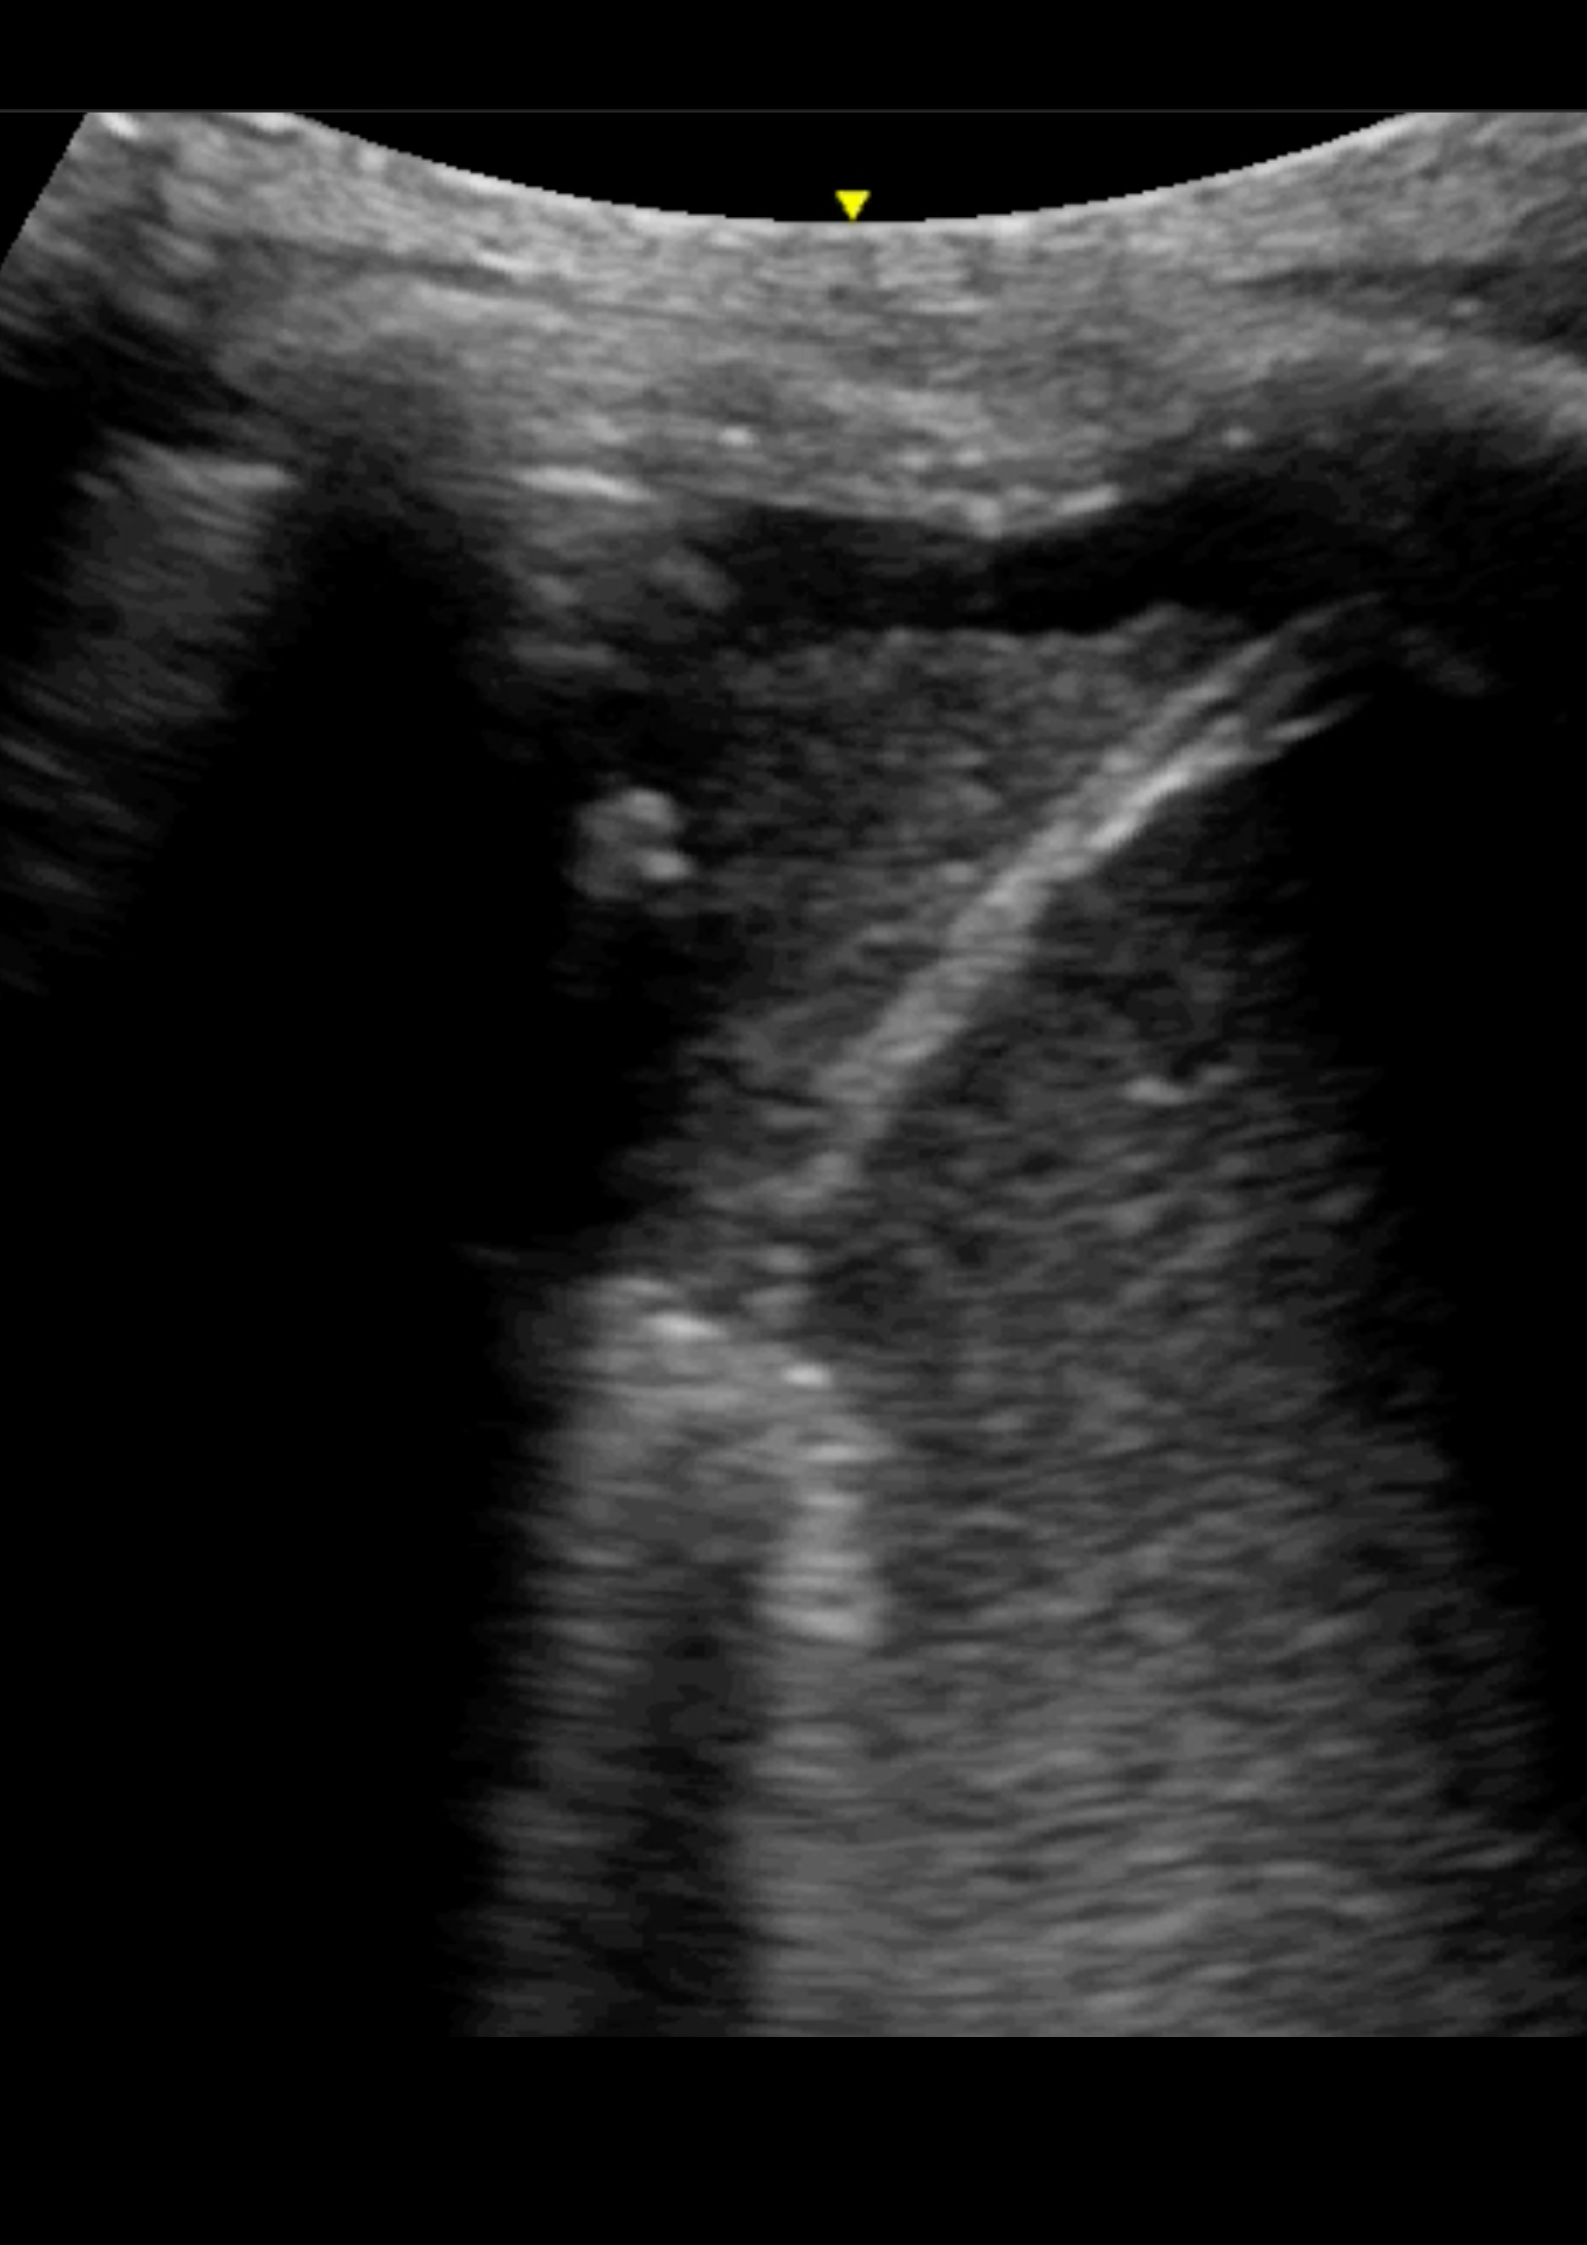

Hallazgos ecográficos

En la ecografía pulmonar observamos varios patrones de líneas B bilaterales de predominio derecho, con hallazgo de consolidación en punto PLAPS (posterolateral alveolar and/or pleural syndrome) y derrame pleural.

La ecografía pulmonar en Atención Primaria no está tan establecida como en el caso de Urgencias, sin embargo, un correcto manejo de la misma permite diferenciar entre diferentes motivos de disnea como son la descompensación cardíaca y el broncoespasmo, así como patología infecciosa. El punto PLAPS, situado en la parte postero-inferior-lateral del pulmón, es el punto más rentable para el diagnostico de las consolidaciones pulmonares así como el derrame pleural, independientemente de la posición del paciente.